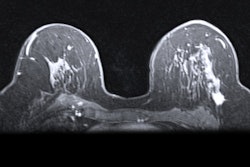

Breast cancer incidence rates have risen over the past two decades among younger women, a study published January 26 in JAMA Network Open found.

Researchers led by Adetunji Toriola, MD, PhD, from Washington University in St. Louis found higher incidence rates among non-Hispanic Black women ages 20 to 29 and 30 to 39. They also found higher incidence rates for estrogen receptor (ER)-positive, stage I, and stage IV tumors.

Breast cancer in young women has a less favorable prognosis compared with older women, with cancers in younger women more likely to have aggressive biological features. Furthermore, women younger than 40 are not recommended for regular screening mammography.